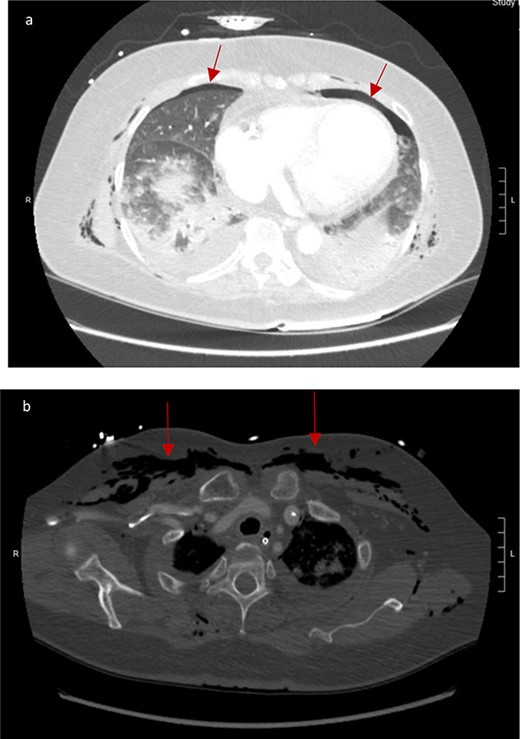

CT scan showed small bilateral pneumothoraces (Fig. 1a) in the setting of several mildly displaced anterior rib fractures with associated subcutaneous emphysema (Fig. 1b), as well as extensive intraperitoneal (Fig. 2), extraperitoneal and retroperitoneal (Fig. 3) air. However, imaging was negative for evidence of perforation. Given concern for abdominal compartment syndrome as evidenced by abdominal distension on exam, initially elevated peak pressures to 24 immediately following intubation, and CT findings of pneumoperitonum, the General Surgery service was consulted for evaluation and further assistance with management. On clinical exam, the patient’s abdomen was distended without tenderness, guarding, or rebound. Laboratory results were notable for white blood cell count of 21.1 per mm3, platelet count of 314 per mm3, and a whole blood lactate of 8.1 mmol/l. Her leukocytosis, though only mildly increased from her baseline of 15 over the previous days, was attributed to known Staphylococcus bacteremia for which she was on antibiotic therapy with a contribution from her shock and PEA arrest. Given the patient was hemodynamically stable with no signs of an acute abdomen, we decided to manage with serial abdominal exams without operative intervention. The patient was closely followed over the subsequent 5 days, during which time she remained stable; she no longer required pressors and was weaned to trach collar on post-arrest Day 2; her white blood cell count continued to downtrend and normalized post-arrest Day 7 as she remained on antibiotic therapy; no additional abdominal imaging was obtained, given her very benign abdominal exam. Operative management was never utilized and she remained asymptomatic. While in the intensive care unit, the patient improved and she was able to engage in physical and occupational therapy despite the pneumothoraces. She was discharged to a long-term acute care hospital on hospital Day 36.

(a) Bilateral anterior pneumothoraces; (b) moderate volume of subcutaneous emphysema in the anterior chest wall.